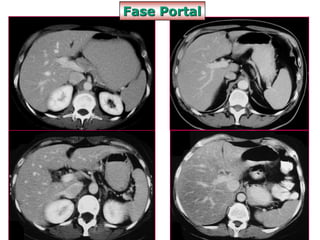

Fase Portal

• Contraste dentro das estruturas venosas,

aspecto homogêneo

• Cortes de 1mm

• Débito de 2ml/s bomba injetora

• Delay 70-80 segundos

• Permite a avaliação da maior parte das

patologias